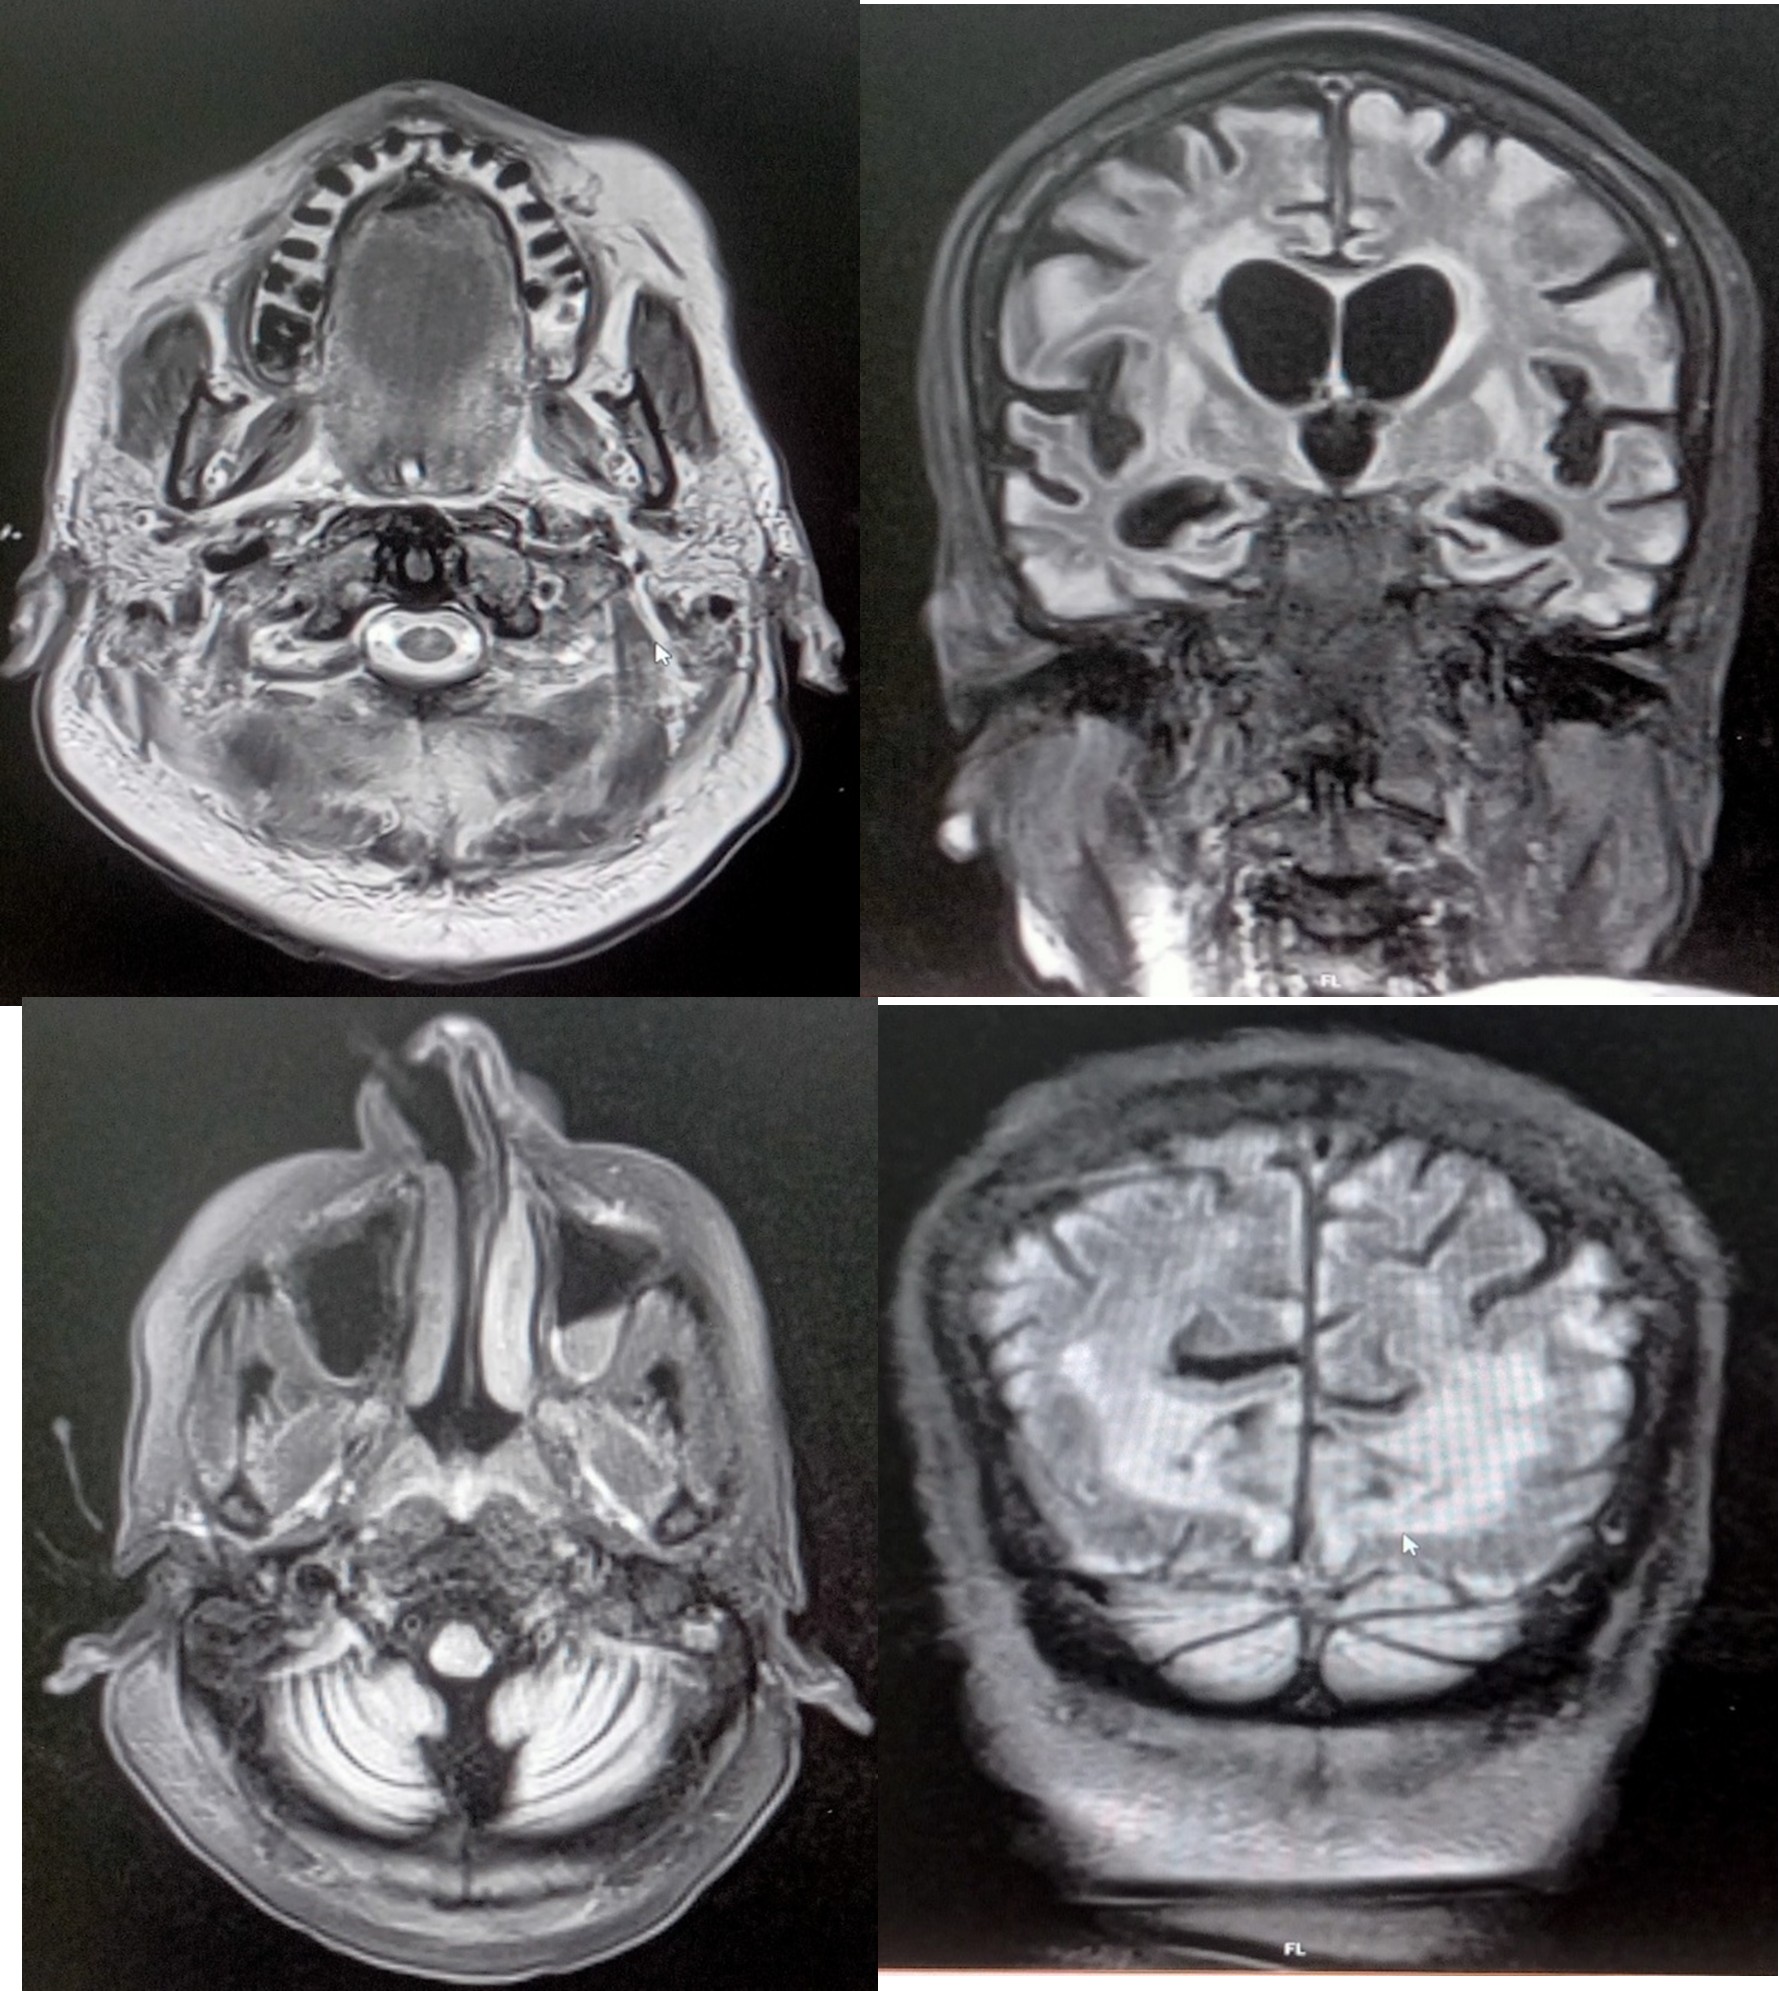

Radiology investigation

- Multifocal acute infarct bilateral parietal, right frontal and periventricular cortex

- Diffuse cerebral atrophy. Small vessel ischemic disease

She was admitted under cardiologists and diagnosed as MI managed as IW PWMI CAG done for the patient and found to have triple vessel disease and advised PTCA and underwent elective PTCA with stenting to proximal to mid RCA & mid to distal RCA with successful result. Post cardiac arrest, she was in poor sensorium with recurrent episodes. Neurologist opinion obtained and managed. The patient was extubated and IABP removal was done in view of persisted seizure activity MRI Brain was taken for patient it showed acute infarct MCA territory and bilateral fronto parietal cortex minimal mass effect and diffuse cerebral edema, cardio embolic etiology was considered.